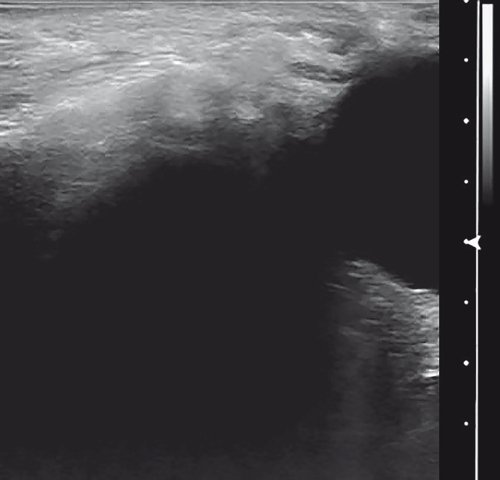

Пациент Н., 43 лет, обратился с жалобами на затруднение носового дыхания, стекание слизи по задней стенке глотки, дискомфорт в левой скуловой области, головные боли. При УЗИ пневматизация правой верхнечелюстной пазухи сохранена, в нижнем отделе вблизи передней стенки визуализируется киста размерами 11 х 9 мм (рис. 5а), левая верхнечелюстная пазуха безвоздушна (рис. 5б), картина напоминает экссудативный синусит, однако задняя стенка имеет двойной контур, и этот признак указывает на то, что это не свободный экссудат, а крупная киста, что и подтверждается результатами МСКТ (рис. 5в, г).

б) Эхограмма левой верхнечелюстной пазухи в В-режиме. Стрелками отмечена стенка кисты.